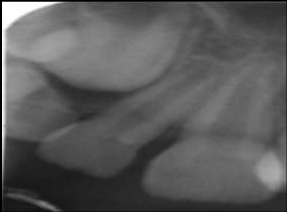

Radiographic findings:

Introral periapical radiograph of the concerned area showed marked bone loss and diffuse radio-opacities in flocculent pattern over the first and second premolar along with the displacement of the teeth. Occlusal radiograph revealed a tooth like calcified mass between first and second premolar. Migrated second premolar was also evident [Figure 4].

Figure 4: Radiograph revealing a calcified mass between premolars.